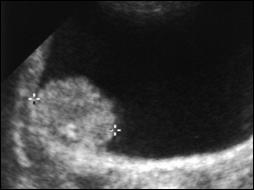

4.2. Ecografia vezicala

Detectarea tumorilor vezicale superficiale, cu grad jos de displazie potential curative, prin tehnici non-invazive ramane o problema nerezolvata [103].

Ecografia vezicii urinare poate aduce date generale importante in diagnosticul tumorilor vezicale superficiale. Este o investigatie strict morfologica ce prezinta mai multe avantaje, fiind nedureroasa, non-invaziva, nu determina efecte secundare, nu are nici un fel de contraindicatie si este repetabila la nesfarsit.

Ecografia vezicii urinare se poate executa pe cale abdominala, transrectala sau transuretrala. Tumorile vezicale apar la ecografie ca mase exofitice, ecodense, intracavitare, fixate la perete, care nu-si schimba pozitia odata cu schimbarea pozitiei pacientului, cu perete vezical normal adiacent tumorii.

Figura 34. a,b. Aspecte ecografice de tumora vezicala - transductor abdominal.

Figura 35. Aspect ecografic de tumora vezicala-transductor transuretral [dupa 132].

Figura 3 a,b) Aspecte ecografice de tumori vezicale. Formatiuni exofitice protruzive intravezicale.

Unele studii acorda ecografiei posibilitatea de a diagnostica o tumora vezicala in proportie de 80% [85]. Cu toate acestea, ea nu poate pune diagnostic de certitudine, ci completeaza celelalte investigatii.

Daca in cazul tumorilor exofitice, diagnosticul de tumora prezenta in vezica nu este greu de pus, stadierea tumorii este practic imposibila ecografic, desi au fost incercari in acest sens.

Chiar folosind transductor transuretral, stadierea nu este de finete; se pot confunda usor tumorile T1 cu T2 si T2 cu T3 [251].